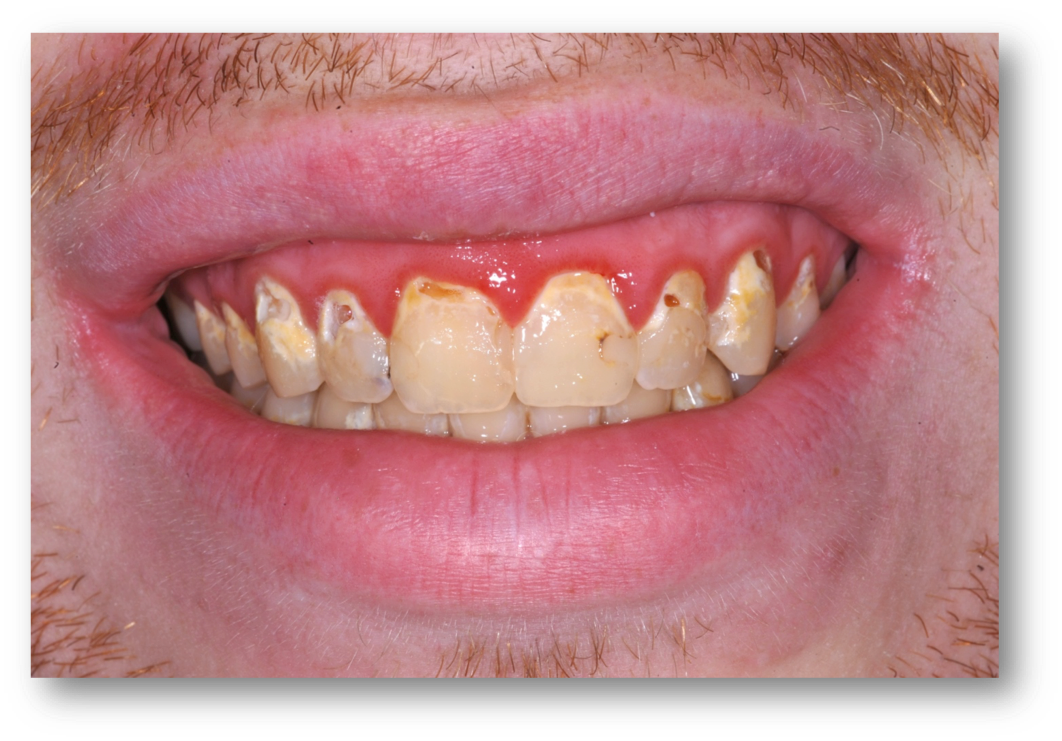

Example 2: Red Gingiva

Red gingiva, as seen in Figure 3, may be caused by a variety of factors, including a lack of brushing, allergies, or drug abuse. Before making a treatment plan, it is important to talk with the patient to try to understand the cause of red gingiva, worn dentition, or erosion.

Fig 3. Red gingiva may be caused by a variety of factors.

Figure 3